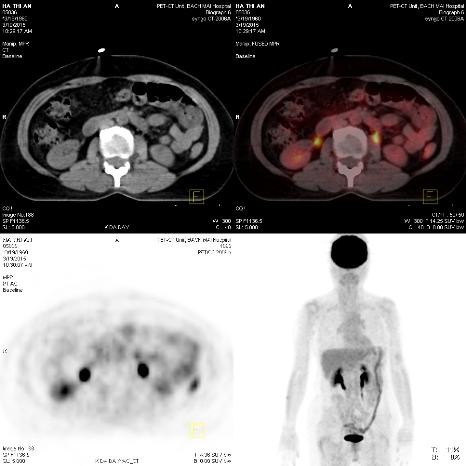

Trước điều trị:Hình ảnh hạch ổ bụng trước điều trị 3 chu kì hóa chất

Sau điều trị: Hình ảnh hạch ổ bụng sau điều trị 3 chu kì hóa chất: Hạch ổ bụng đã tan hết. (Mũi tên xanh: không còn tổn thương)

Hình 9: Hình ảnh so sánh trước và sau điều trị 3 chu kì hóa chất